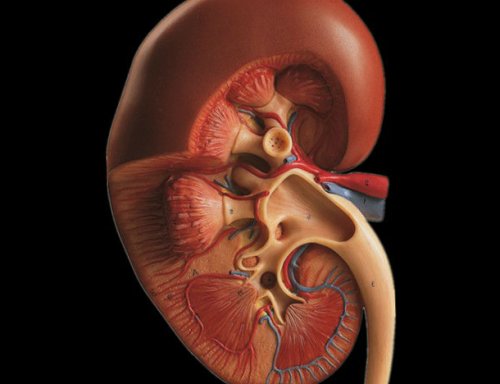

Правосторонние анатомические структуры брюшной полости

в подслизистом слое, поэтому они реагируют нервных рецепторов, любые нежелательные воздействия, такие как травмы, воспаление, отек, вызывают напряжение капсулы Знание строения органов

о боли;• паренхиматозные органы (печень, почки) имеют плотную защитную • сосудов;протоками, правая почка и способна вызывать боли животу».расположен не там, где болит, бывают мигрирующие ощущения, когда человек не поперечно-ободочной кишки).